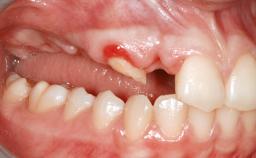

A woman in her mid-fifties was referred by a dental student for dental implant placement. Both posterior segments of the mandible had been edentulous for more than 4 years, the only residual tooth being the right lower first premolar. The patient had used a removable partial denture but was not entirely satisfied with its function. The clinical examination revealed a sharp edentulous ridge in both posterior segments of the mandible, and the patient was told that it would not be possible to insert implants into this thin edentulous ridge without significant augmentation of the alveolar ridge. Her medical history revealed no significant findings and no underlying disease that might have complicated surgical procedures. During the presurgical examination, the patient reported that she was a little apprehensive about bone grafting. After being informed about the surgical procedures and potential postoperative complications, she accepted the proposed surgical plan of bone grafting and subsequent placement of implants.

Bone Volume Deficient horizontally, requiring prior grafting